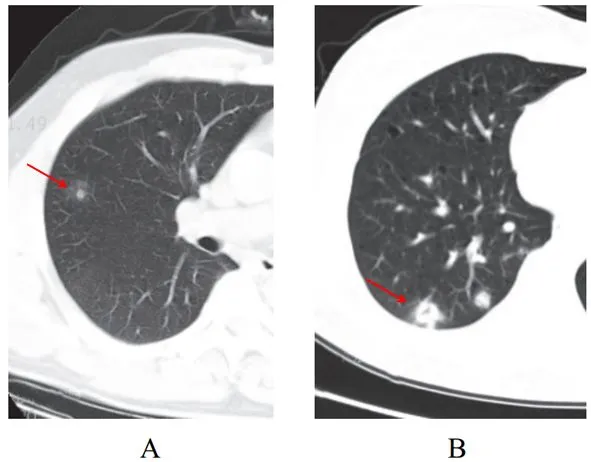

(五)结节伴晕征

部分案例实性结节病灶周围出现磨玻璃密度影,边缘模糊,称为晕征

根据既往病理学机制提示,病灶中心实变影为肺泡腔内聚集大量富细胞渗出液,显示为实性密度灶;其周围肺泡亦见渗出,包含炎症细胞、蛋白质、纤维素等,形成“膜状物”,或形成磨玻璃密度阴影(图 2-5)

图 2-5 结节伴晕征(A和B)